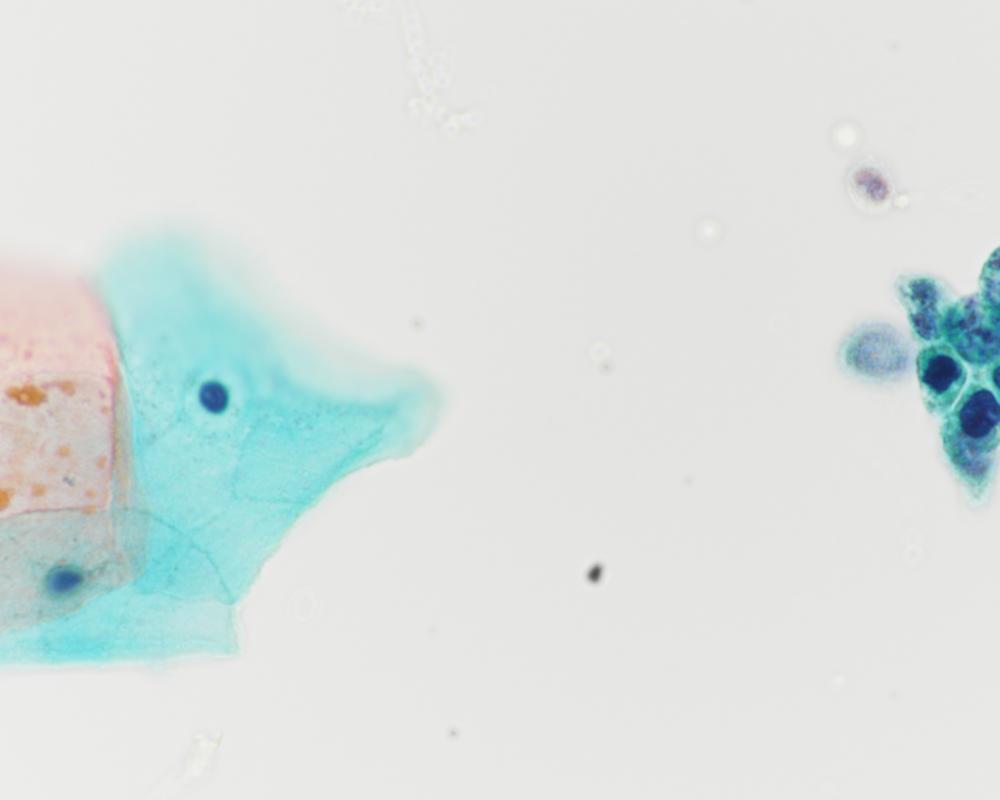

種別:呼吸器

| 採取部位 | 肺腫瘍 | 採取方法 | 捺印 |

既往歴:59歳 前立腺癌に対してホルモン治療、放射線治療、59歳高血圧、63歳糖尿病で内服加療中

現病歴:前立腺癌の経過観察のCTにて右肺結節を指摘された。PSA含めて腫瘍マーカーは正常であった。本標本は術中迅速組織診断用に提出された肺腫瘍の捺印細胞診検体である。

| 正解 | 5.転移性肺腫瘍(前立腺癌) |